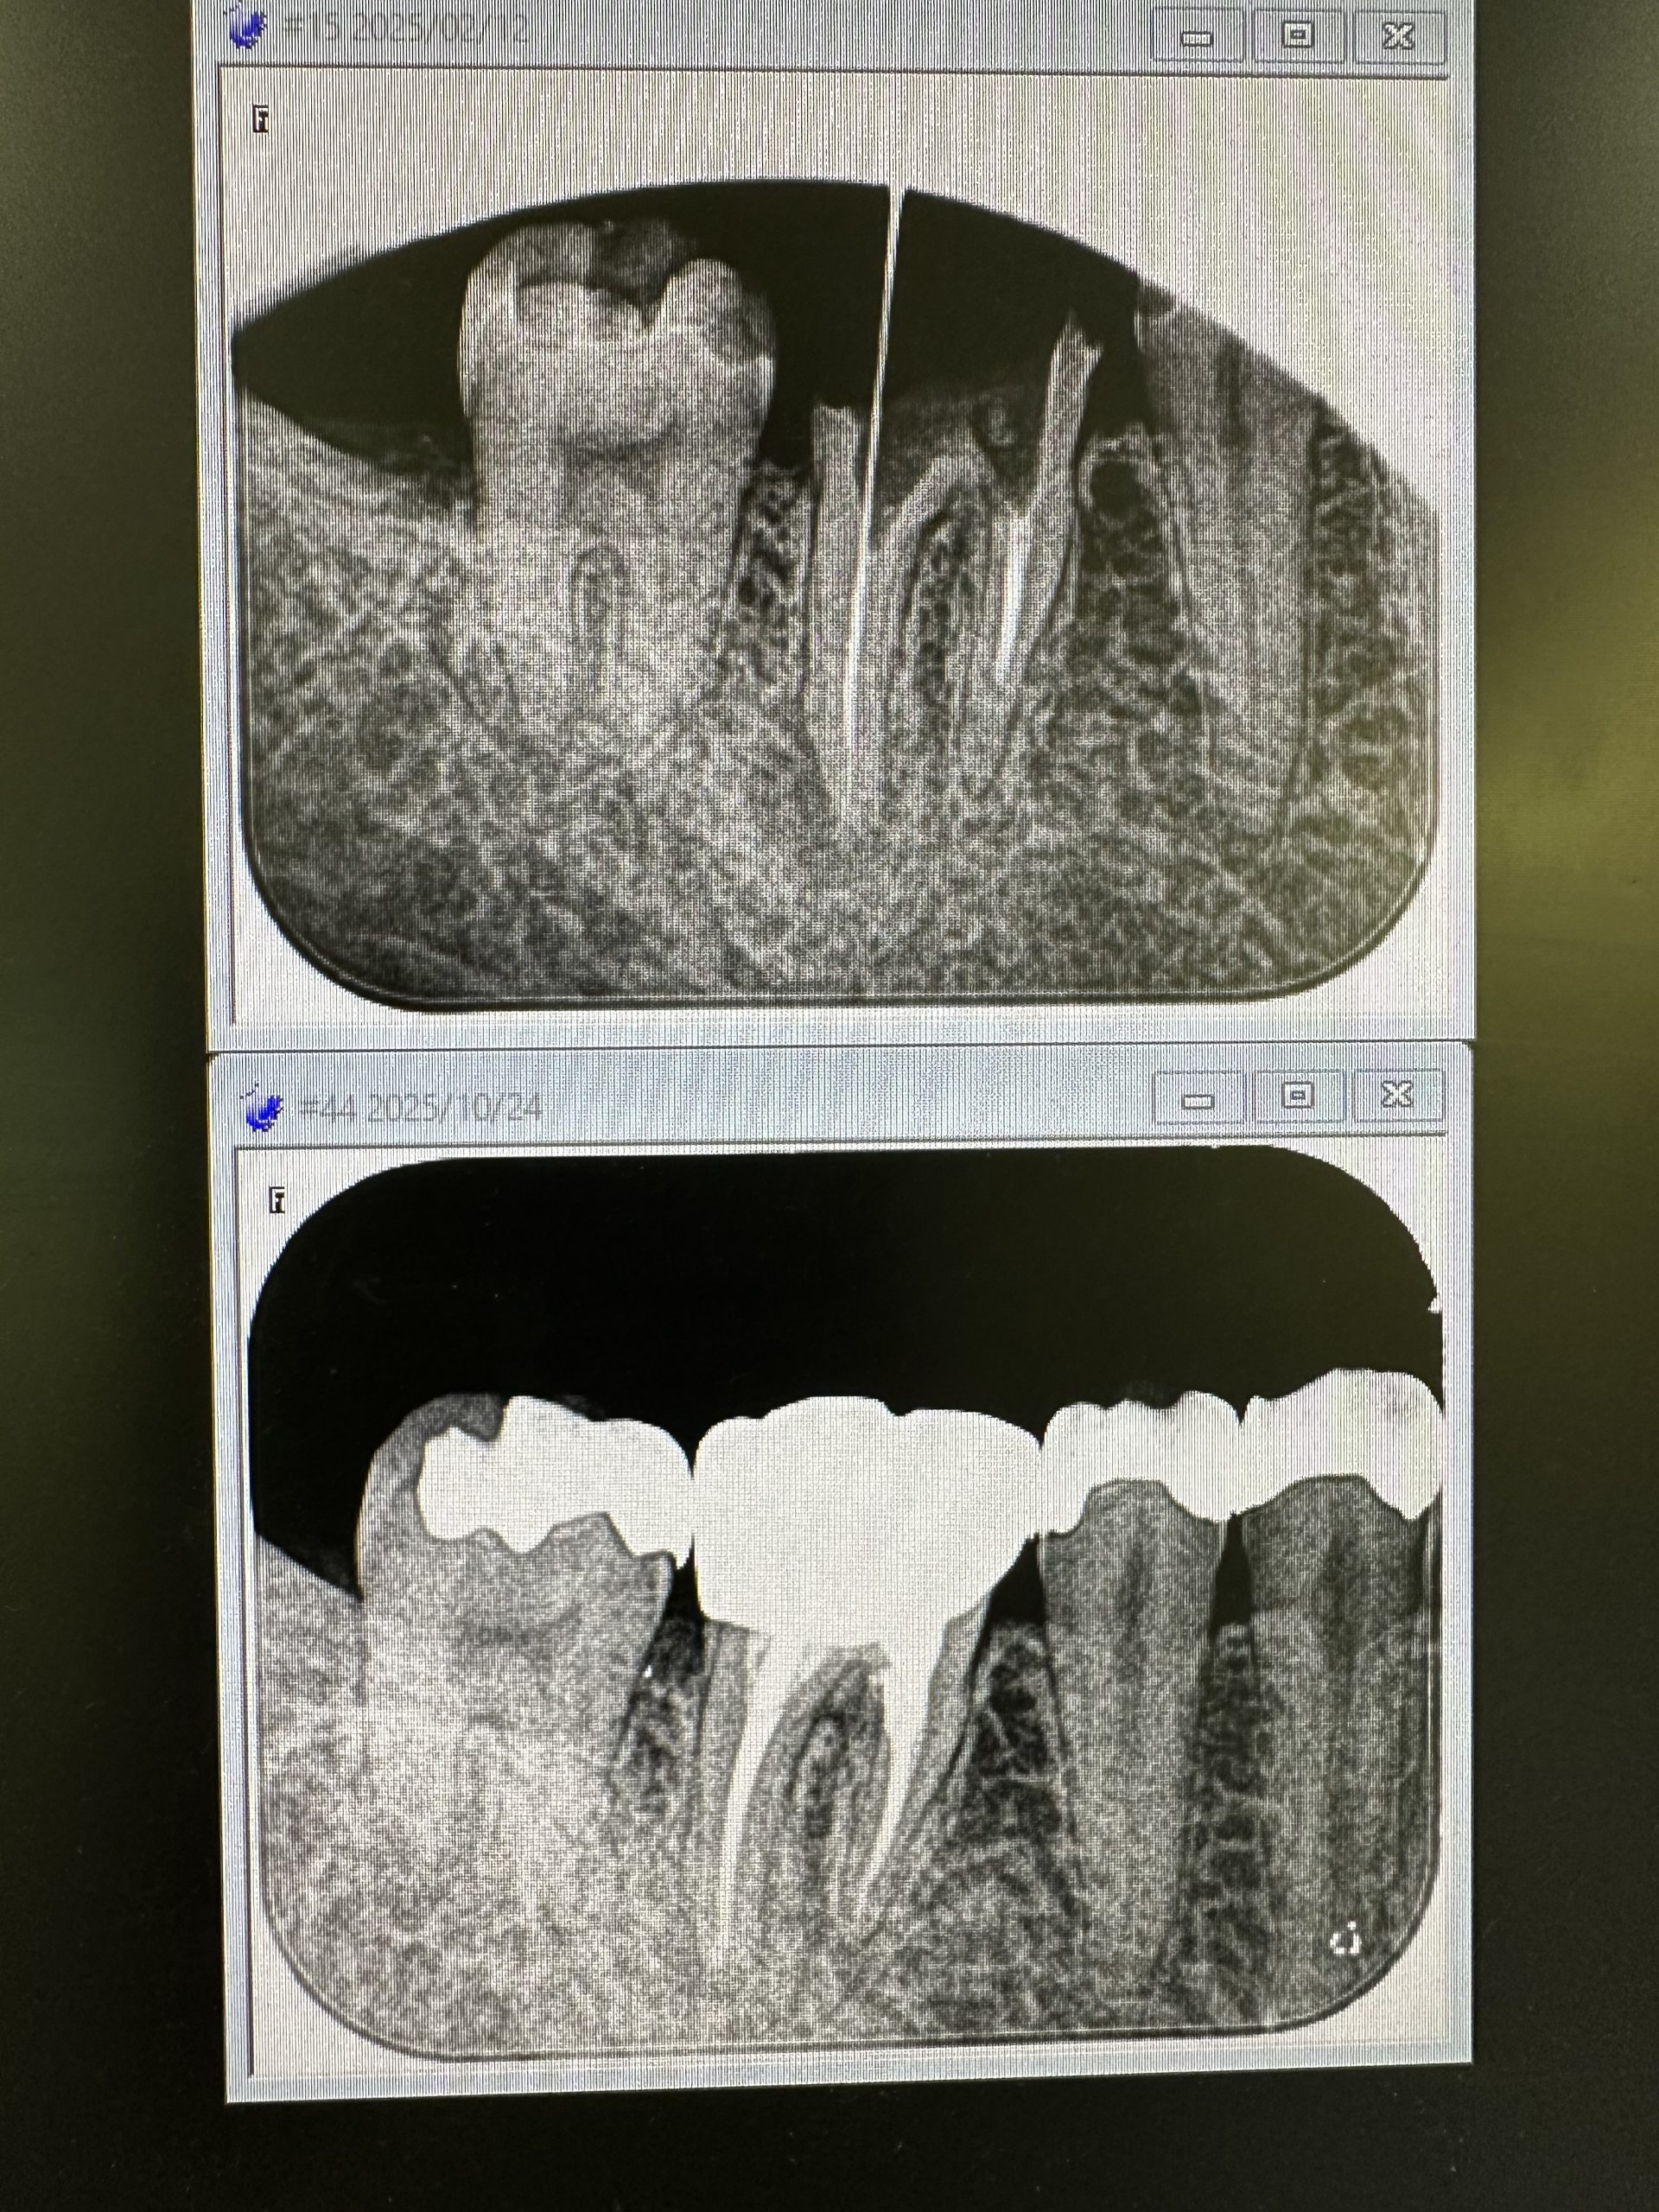

根管治療経過、良く治ってきてる💪

マメに殺菌、消毒、長さ測りネチッコくやれば誰でも上手くいきます